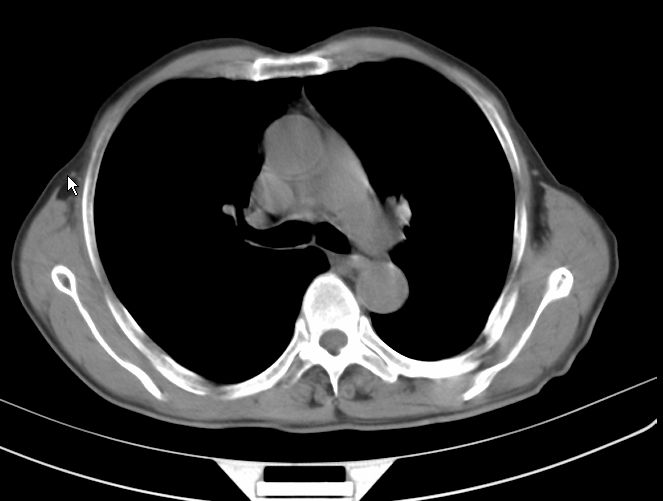

标题: CT17095:胸部病变请大家看看是什么性质的

请大家看看是什么性质的。炎性病变首先考虑哪一种炎症。

支持右肺上叶前段\\下叶内基底段感染,建议抗炎治疗后复查,除外结核.

支持右肺上叶前段\\下叶上段感染,建议抗炎治疗后复查,除外结核.

支持右肺上叶前段、下叶内基底段感染,建议抗炎治疗后复查,除外结核.

右肺上叶前段及下叶内基底段感染性病变;建议抗炎治疗后复查。

楼主说是炎症,凭啥?典型的周围型肺癌(腺癌可能性大),肝内可能已有转移,强化看看吧。